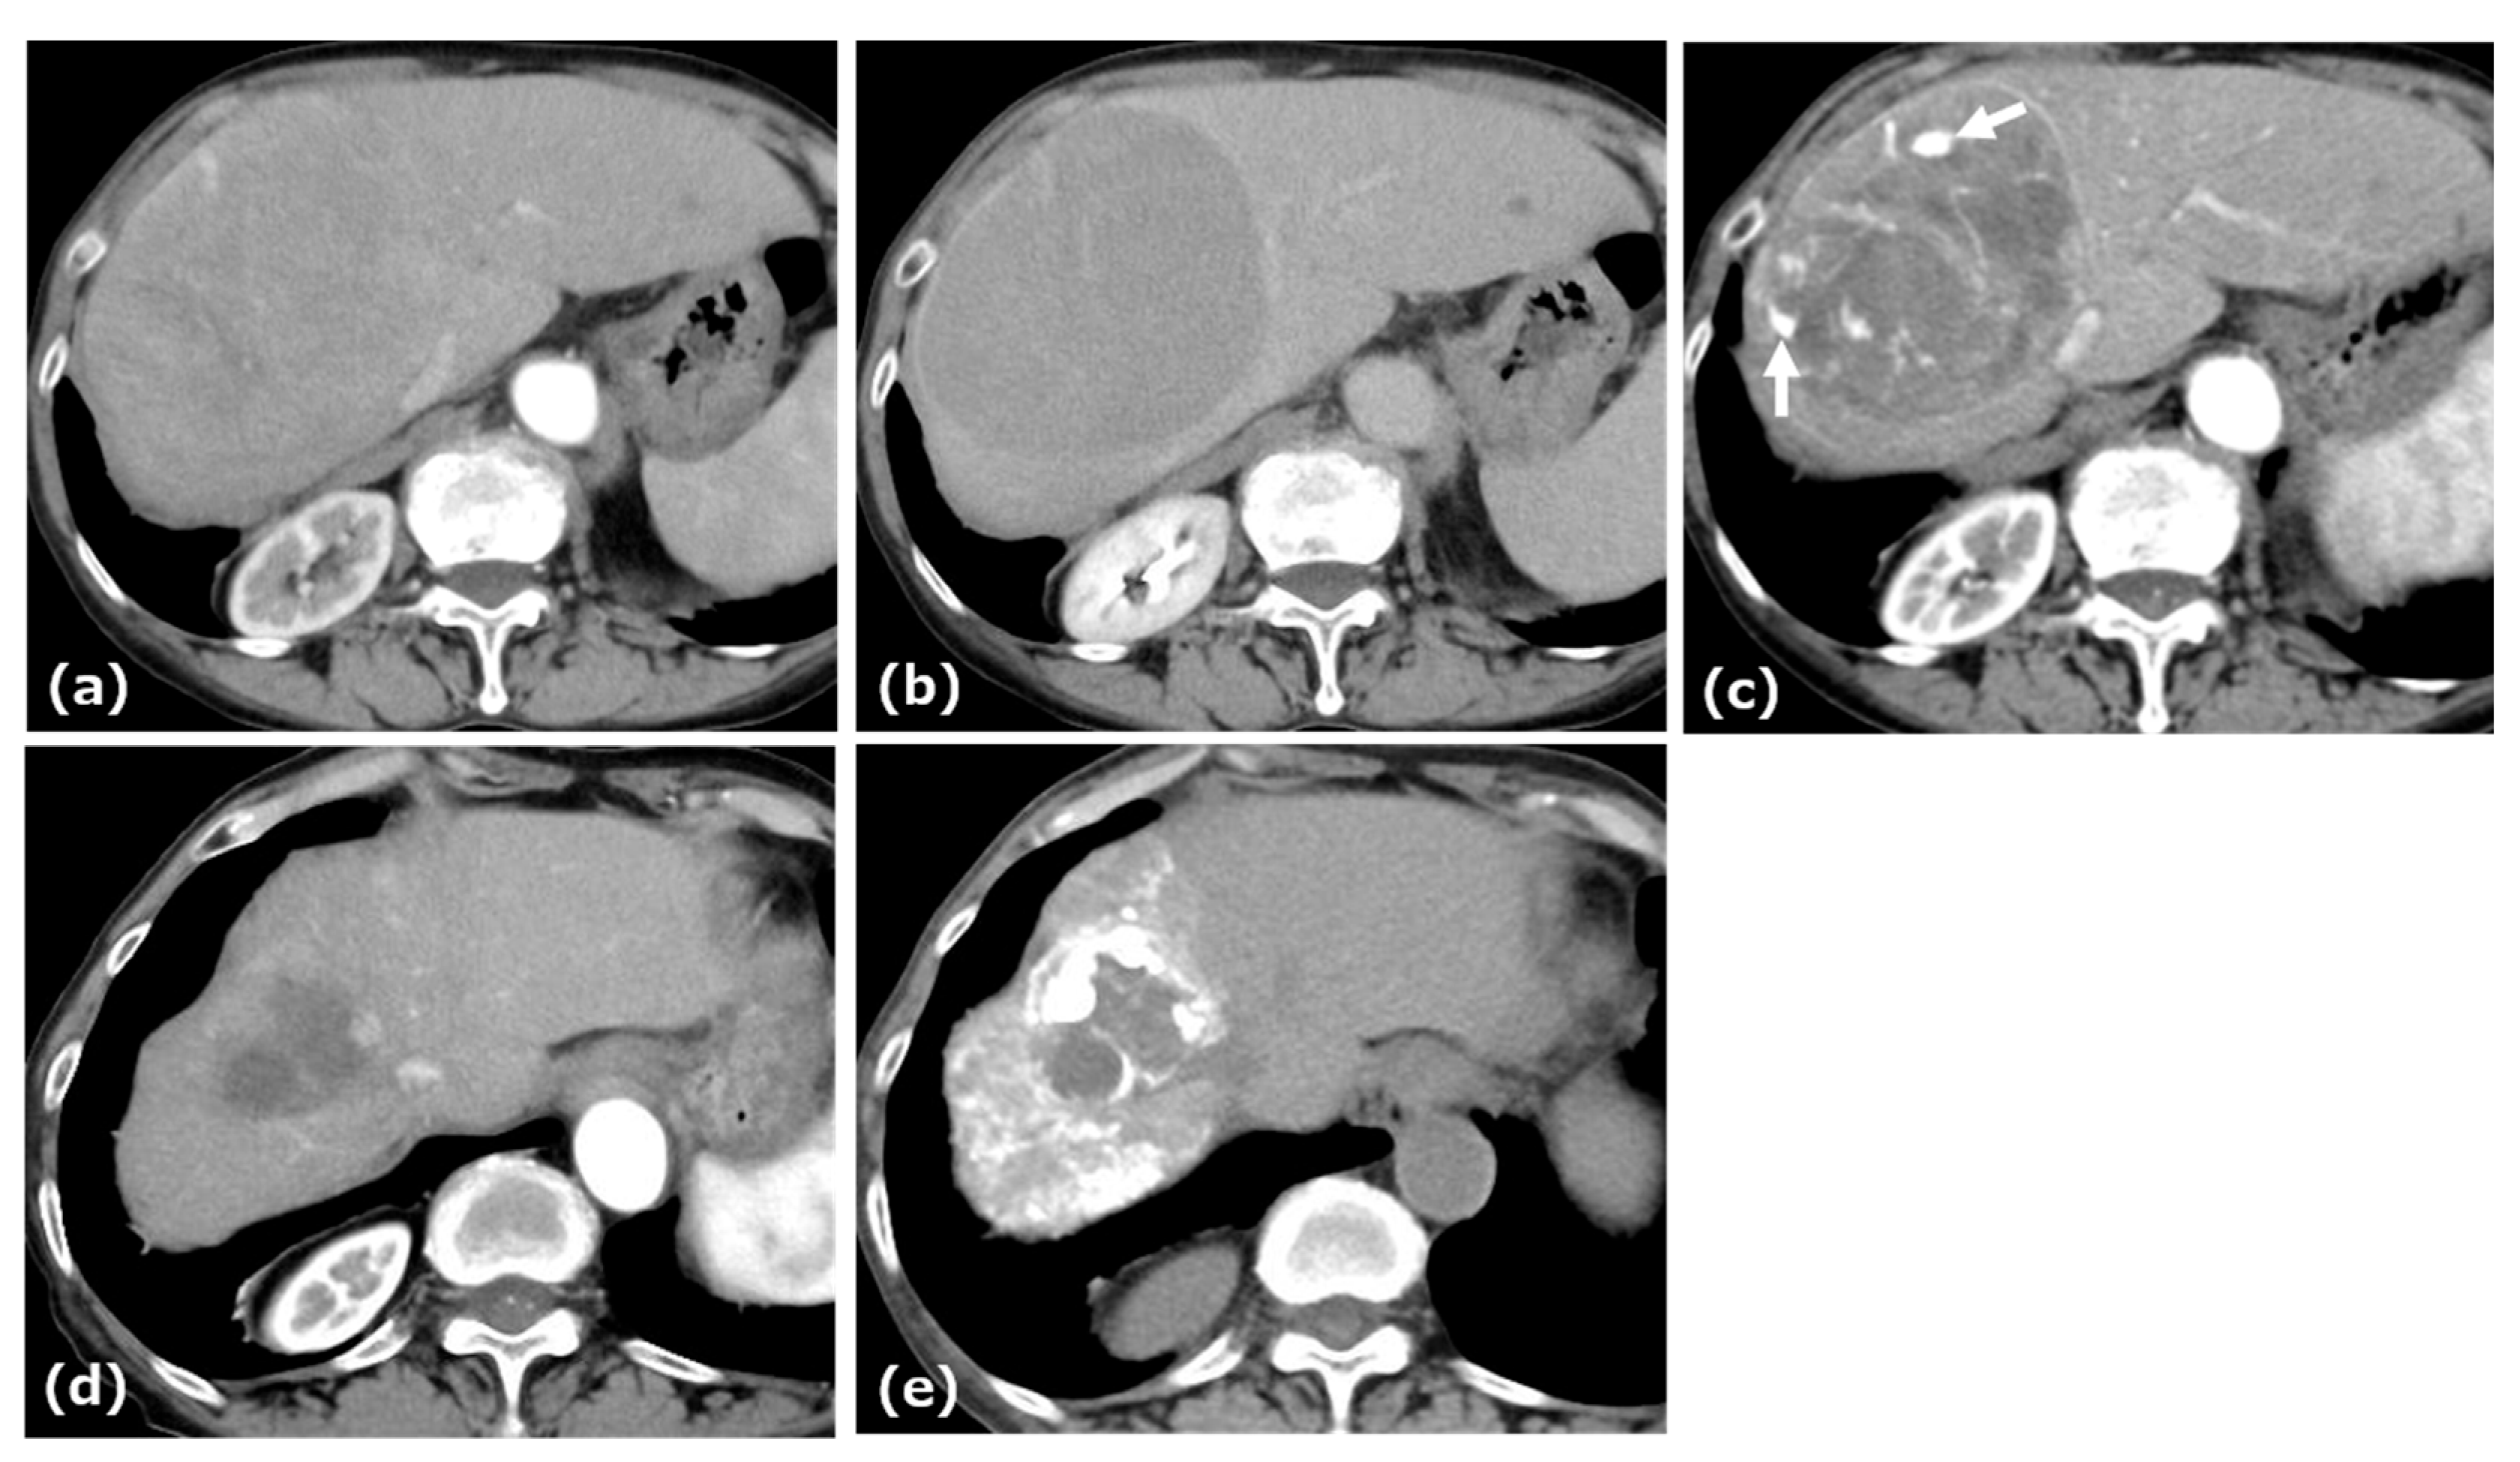

2.1. Case 1